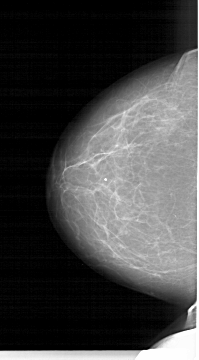

A_1264_1.LEFT_MLO

LEFT_MLO LINES 6466 PIXELS_PER_LINE 3511 BITS_PER_PIXEL 12 RESOLUTION 43.5 NON_OVERLAY